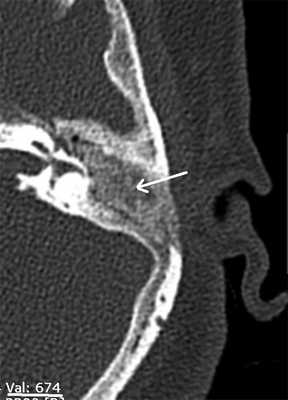

МСКТ височных костей проводилась через год после операции с целью оценки состояния реимплантированной костной ткани.

Анализ данных МСКТ показал, что реимплантрованная костная ткань имеет меньшую плотность, чем наружный кортикальный слой сосцевидного отростка, и варьировала от 350 до 680 едН. В подавляющем большинстве исследований по данным МСКТ не визуализировалась четкая граница между пересаженной костной стружкой и окружающей костной тканью (рис. 3). Лишь в 6 (18%) случаях можно было наблюдать тонкую прослойку низкой плотности между реимплантированной и окружающей костной тканью. По плотности данная прослойка сопоставима с соединительной тканью. Данные МСКТ также позволили в 2 случаях (8%) предположить рецидив холестеатомы. Этим пациентам была выполнена санирующая реоперация по открытому типу (с формированием МП). Интраоперационные находки подтвердили данные МСКТ височных костей и необходимость реоперации.

Рис. 3. МСКТ левой височной кости, аксиальная проекция. Стрелка — имплантированная костная стружка.